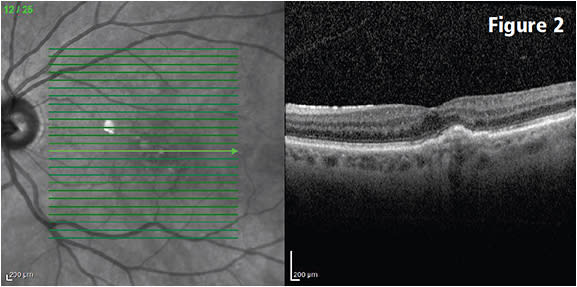

In addition, treat-and-extend strategies can lessen the burden on practices as well as patients (Figures 1-3).

Figure 2: Three months after the baseline visits, following three monthly bevacizumab injections. Mild subfoveal elevation of the retinal pigment epithelium with resolution of all macular fluid. Visual acuity improved to 20/40. COURTESY CHRISTOPHER HAUPERT, MD